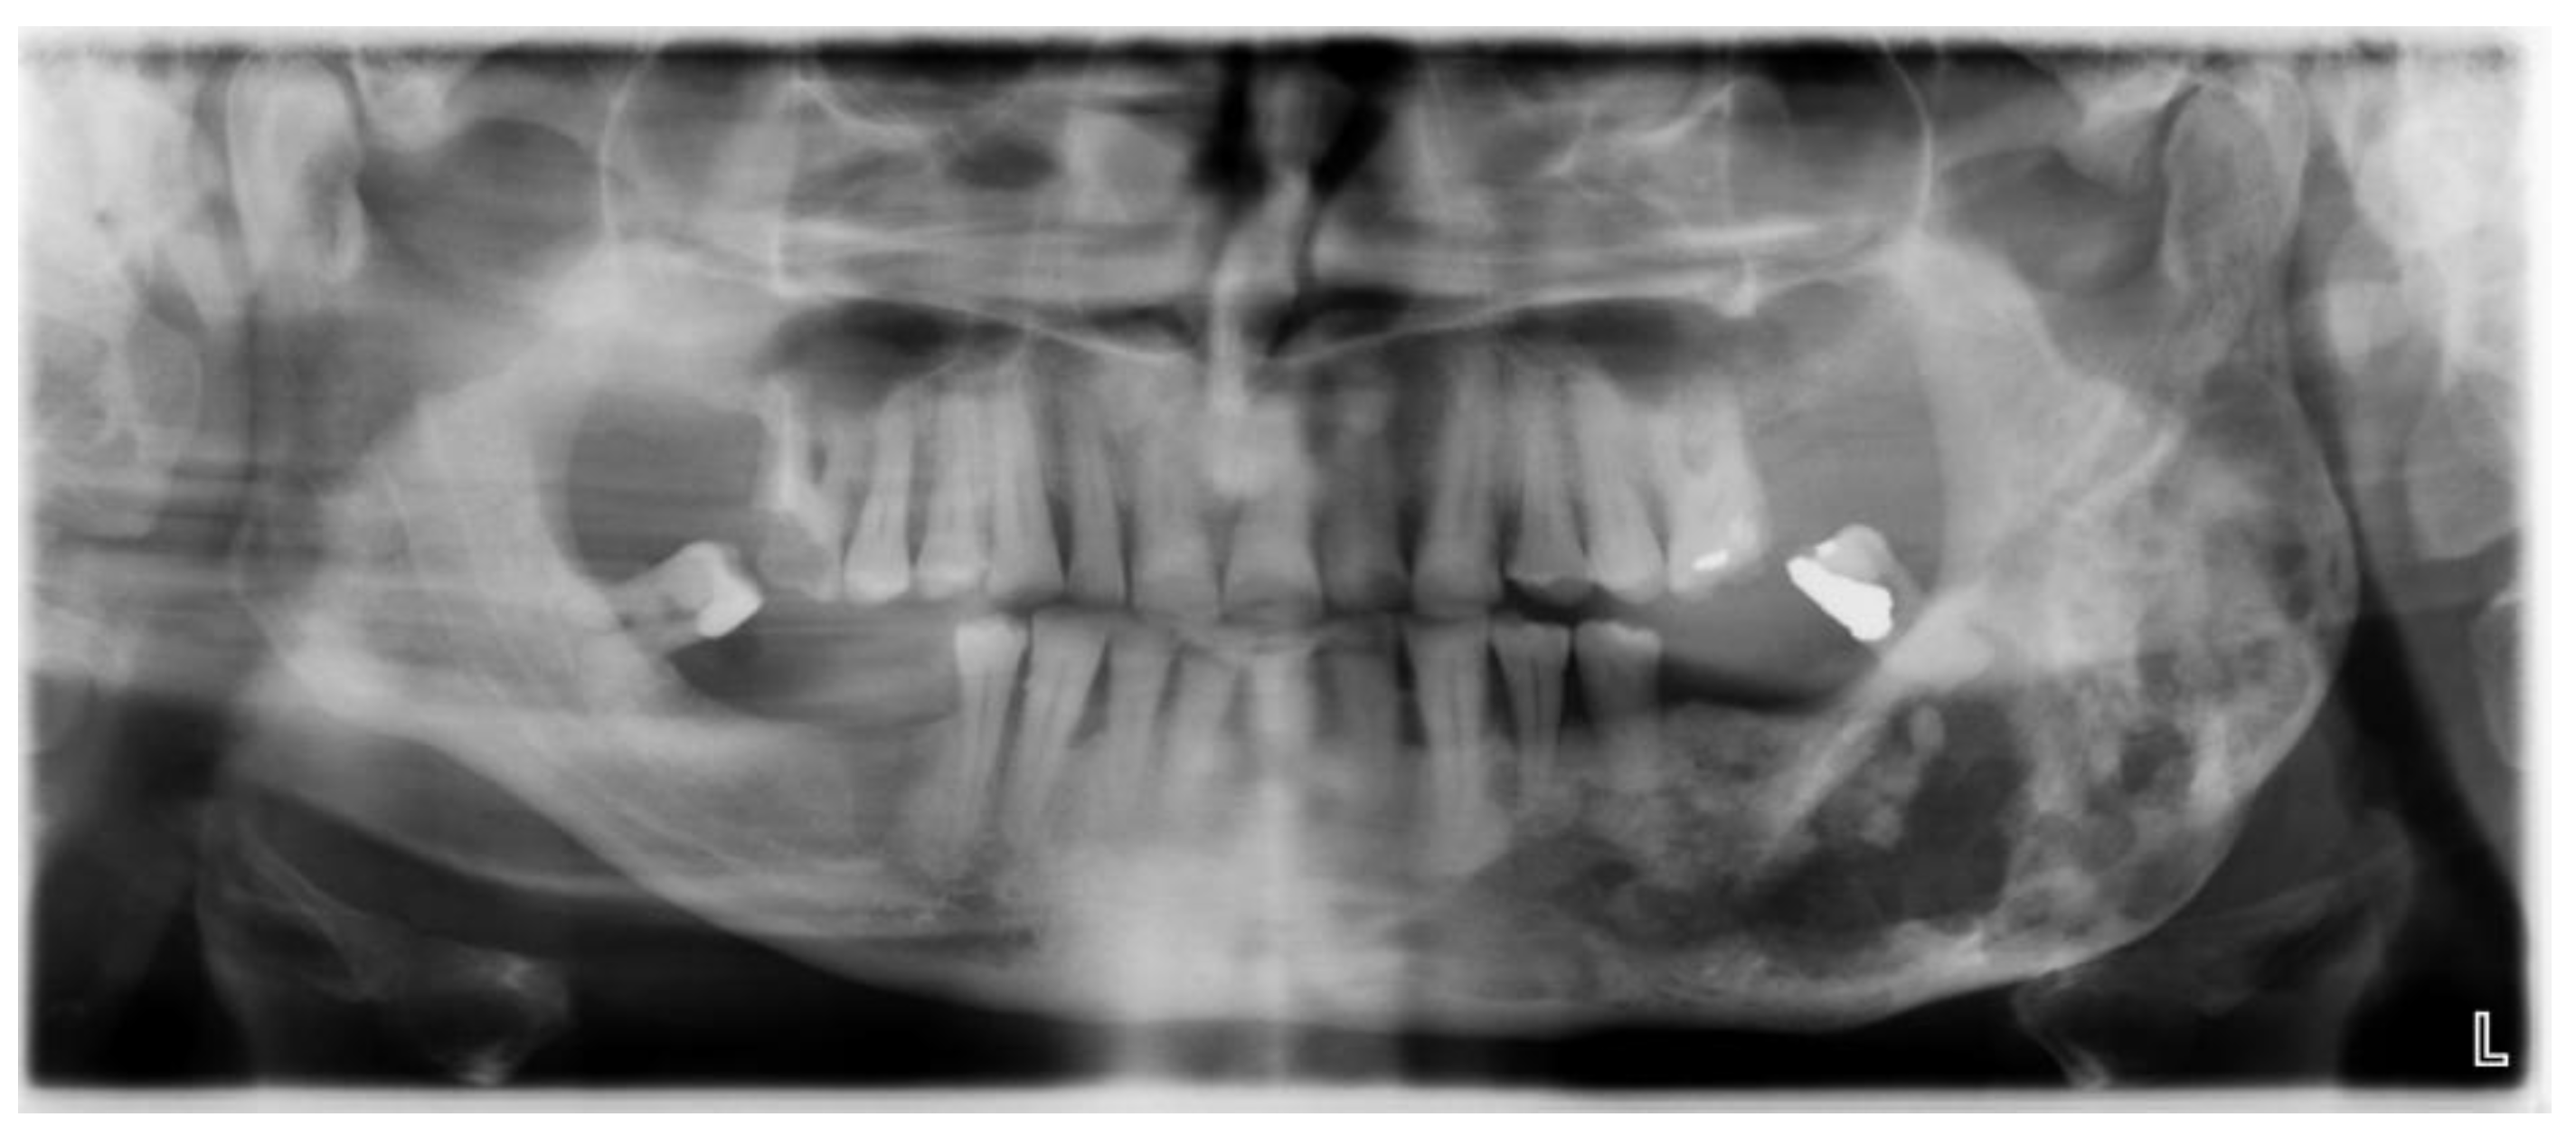

- phase 1: Conversion of the CT scan of the mandible from DICOM format to a 3D STL model